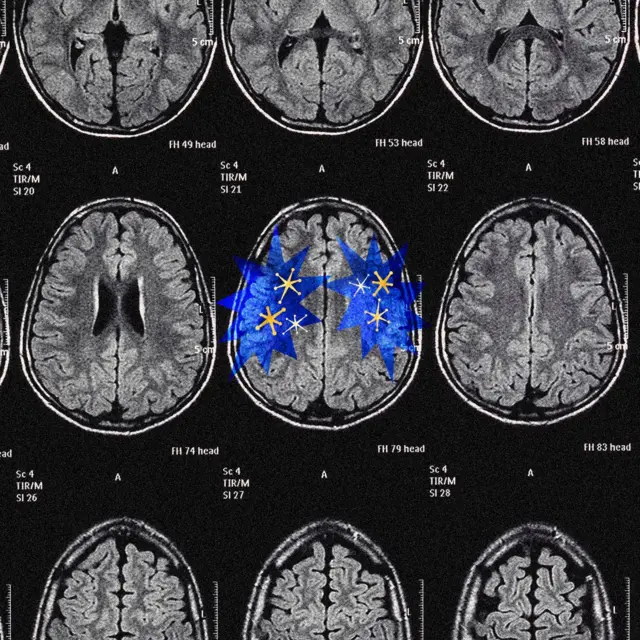

要理解原因,我们需要看看大脑中两个部位——大脑皮层(cerebral cortex)与包括多巴胺在内的奖赏系统——如何驱使我们朝不同方向前进。

显然,这套机制并不完整:必然还有某种力量,推着皮层走出无经验的黑暗房间,进入充满新奇、惊喜、目标与成就的世界。事实上,大脑确实有另一个模组,其整个存在目的,就是策动这样的推力。它就是奖赏系统,而多巴胺便是这个系统用来引导我们决策与动机的主要工具,一种既巧妙又近乎魔鬼般的工具。多巴胺让我们持续往前走。

图像来源,Serenity Strull